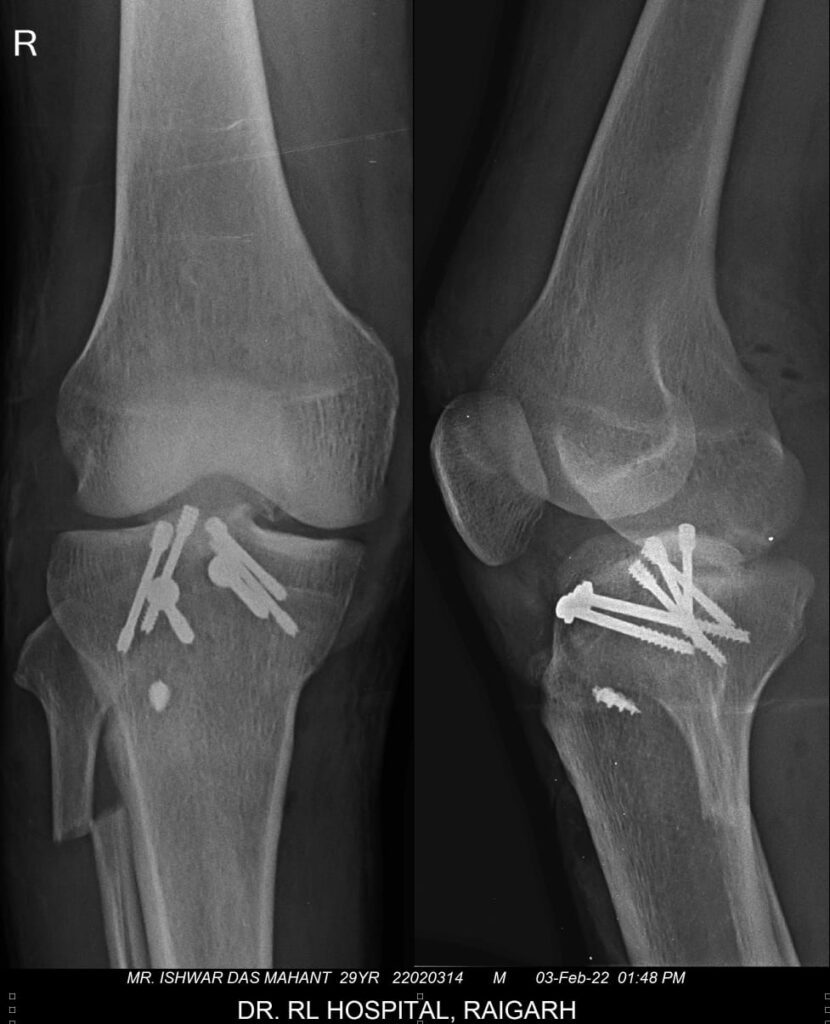

भगत(एम.एस.सर्जन आर.एल.अस्पताल के नियमित सर्जन)द्वारा पहले मरीज के दोनों फेफड़ों में चेस्ट ट्यूब डाला गया। मरीज की हालत में सुधार होने के बाद चेस्ट ट्यूब चार दिनों के पश्चात निकाल दिया गया।मरीज के स्थिर होने के बाद डॉ. प्रशांत अग्रवाल के नेतृत्व में मरीज के घुटने का अत्यधिक जटिल ऑपरेशन किया गया।लगभग चार घण्टे तक चली इस सर्जरी में डॉ.प्रशांत ने हड्डी को स्क्रू से जोड़ा और लिगा मेन्ट को स्क्रू से फिट किया।फिर मरीज के घुटने के पीछे तरफ के कैप्सूल और टेंडम को रिपेयर किया गया।डॉ. प्रशांत एवं उनकी टीम ने मरीज के घुटने का सफल इलाज कर उसे फिर से चलने फिरने में सक्षम किया।बता दें की इस तरह के जटिल ऑपरेशन पहले महानगरों में किये जाते थे।किंतु डॉ प्रशांत अग्रवाल ने इस सर्जरी को करके मरीज को बहुत बड़ी परेशानी से बाहर निकाला।